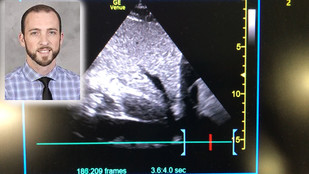

In this image, (inset) Dr. Ryan Reed. The rest of the image is of the subcostal inferior vena cava view that Dr. Reed obtained using point of care ultrasound. (VA courtesy photo)

SYRACUSE, N.Y. – The VHA SimLEARN National Simulation Center (NSC) provides VA clinicians with a wide variety of courses designed to improve their skills, as well as provide our Veterans with an even higher level of care. Oftentimes, the public benefits from the care of a VA physician trained in an NSC course. That was the case recently when Dr. Ryan Reed, chief resident of quality and patient safety at the Syracuse VA Medical Center (VAMC) in New York was moonlighting at a local, private hospital.